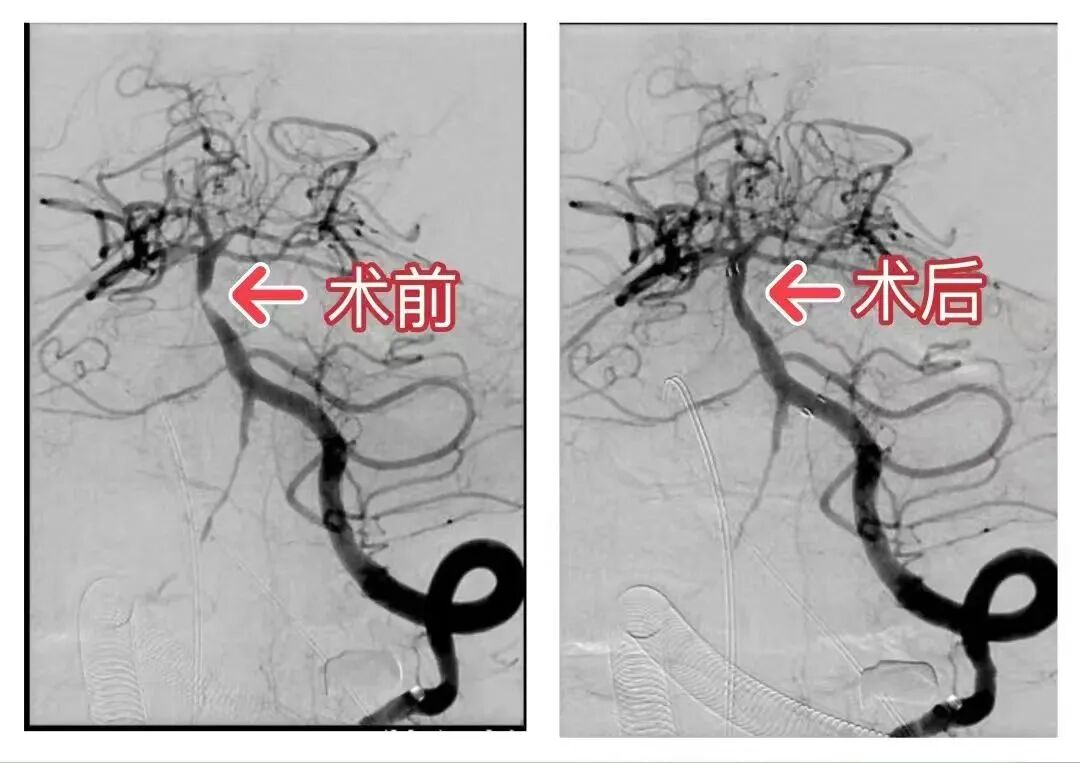

今年63岁的张阿姨患有高血压、糖尿病病史多年,近半年来反复出现发作性头晕、视物成双、黑矇症状,严重时伴有肢体无力。在当地医院住院检查发现基底动脉重度狭窄,但因基底动脉狭窄手术风险太大,当地医院不敢给予介入治疗,长期口服预防血栓药物及定期输液治疗。但由于血管狭窄严重,张阿姨仍有间断症状发作,甚至有一次出现了昏迷意识丧失。张阿姨每天生活在恐惧当中,甚至都不敢出门活动,这种心理状态严重影响患者的正常生活。 张阿姨的家属慕名转入沧州市中心医院脑血管病一科进一步治疗,拟行基底动脉支架介入手术。基底动脉支架置入手术被列为神经介入领域高难度复杂手术之一,基底动脉一旦闭塞患者将发生难以承受的严重后果甚至是生命危险。住院后通过高分辨核磁及灌注成像等检查,显示患者脑血流灌注极差,随时有发生梗死的风险。脑血管病一科董志领主任确定患者介入治疗指征明确,与家属充分沟通后,家属同意行基底动脉支架植入术治疗。 经过一系列术前准备,董志领主任带领脑血管病一科神经介入团队术前认真制定了完善的手术方案,在多学科的配合下,对基底动脉狭窄部位进行了球囊扩张及支架置入,复查造影提示狭窄明显改善,椎基底动脉显影良好,整个手术过程仅用时60分钟。手术后患者头晕、黑曚症状基本消失,术后第三天即康复出院。随访患者未再出现头晕、黑矇及肢体无力等症状。张阿姨也用不再天天担心自己会随时出现脑血栓,回归了正常生活。 基底动脉是人脑血管中最重要的主干血管,供应“生命中枢”脑干及小脑及部分大脑组织。基底动脉具有分支多、管径窄、路径长且迂曲、弹性差、缺血耐受差等特点,支架置入有可能造成分支血管闭塞、血管夹层、血栓脱落、支架内血栓形成、高灌注出血转化等并发症。因此,被视为脑血管支架植入的“禁区”。但近年来随着神经介入技术的快速发展,医院对于包括基底动脉在内的颅内动脉狭窄支架介入手术开展顺利,技术水平及手术例数已位于省内前列,给狮城百姓的健康带来更有效的保障。 脑血管病一科 河北省临床重点专科,国家级临床重点专科创建单位、中国脑卒中专科联盟,沧州市神经内科专科联盟主委单位,河北省医学会脑血管病联盟单位。现有医护人员 37名,其中硕士生导师4名,专业硕士17名,主任医师3名,副主任医师3名,主任护师1名。科室建立了神经介入、脑血管病、脑小血管病、烟雾病血管炎、脑静脉梗死、脑血管康复与预防六个专业组。诊疗范围为短暂性脑缺血发作、脑梗死、蛛网膜下腔出血、脑出血、颅内动脉瘤、脑血管狭窄、脑血管畸形、脑血管炎、静脉窦血栓、脑静脉血栓、脑血管病后遗症、脑动脉夹层、脑淀粉样血管病、遗传性脑血管病、动脉粥样硬化、脑动脉盗血综合症、慢性脑缺血、海绵状血管瘤、动静脉畸形、高血压脑病、脊髓梗死、代谢性脑病等。 科室特色: 1、脑血管病的介入治疗 脑血管造影;脑血管狭窄支架及动脉瘤栓堵术;介入溶栓及支架治疗。 2、急性脑梗死 静脉溶栓、动脉溶栓、动脉取栓、拉栓、桥接、卒中单元。 3、脑小血管病 通过脑小血管病影像学标记物等,准确诊断脑小血管病,采取个体化的治疗。 4、烟雾病 烟雾病是青年卒中患者发病率较高的疾病,通过核磁、脑血管造影能够准确的判断烟雾病并对其进行分期,判断血管代偿的级别,采取药物和搭桥治疗。 5、青年脑卒中 青年脑卒中病因众多,主要是免疫、炎症、卵圆孔未闭、肥胖、药物、家族遗传、基础疾病等。通过病因的诊断确定发病的类型,采取相应的措施达到良好的治疗效果。 6、脑静脉梗死 静脉梗死病因众多,主要是产褥期、高凝、癌症、炎症、脱水、电解质紊乱等,预后较差。通过脑血管造影及病因的筛查能够早诊断早治疗,治疗的都能达到良好的预后。 7、脑血管病的预防、脑血管病后遗症、脑血管病康复、脑血管炎、脑血管狭窄及疑难杂症等方面的诊疗达到国家级水平。 董志领 沧州市中心医院脑血管病一科主任,沧州市中心医院盐山分院院长,主任医师,河北医科大学教授,硕士,硕士生导师。沧州市医学会神经内科分会主任委员,沧州市神经介入研究所所长,沧州市神经科学学会会长,沧州市神经内科联盟理事长,沧州市神经内科质控中心主任,河北省脑卒中专科联盟副主任,河北省医学会神经病学分会脑血管病组副组长,河北省中西医结合学会神经内科专业副主任委员,河北省医学会、医师学会常务委员,中国医师学会神经介入专业委员会委员。 从医三十余年分别在首都医科大学天坛医院,301医院,第四军医大学,山东大学齐鲁医院进修学习急慢性脑血管病、危重症、疑难杂症,脑血管狭窄支架,动脉瘤栓堵治疗。作为沧州市医学会神经内科分会主任委员,沧州市神经内科质控中心主任带领沧州市县级以上医院成立脑卒中中心,使得沧州市脑血管的防治在河北省处于领先水平。擅长脑血管,脑血管狭窄支架,脑动脉瘤栓堵术,脑梗死动静脉溶栓,脑缺血,烟雾病,脑小血管病,脑梗死,脑出血,蛛网膜下腔出血,静脉窦血栓,血管畸形,脑血管狭窄,脑血管硬化,高血压脑病,遗传性脑血管病,疑难杂症等的诊治达到国家级水平。 擅长:脑血管病,疑难重症脑血管病,脑血管狭窄支架治疗,脑动脉瘤栓堵治疗,脑动脉狭窄、脑供血不足、脑梗死溶栓,脑出血,蛛网膜下腔出血,脑静脉窦血栓,脑小血管病,烟雾病,青年脑梗死。